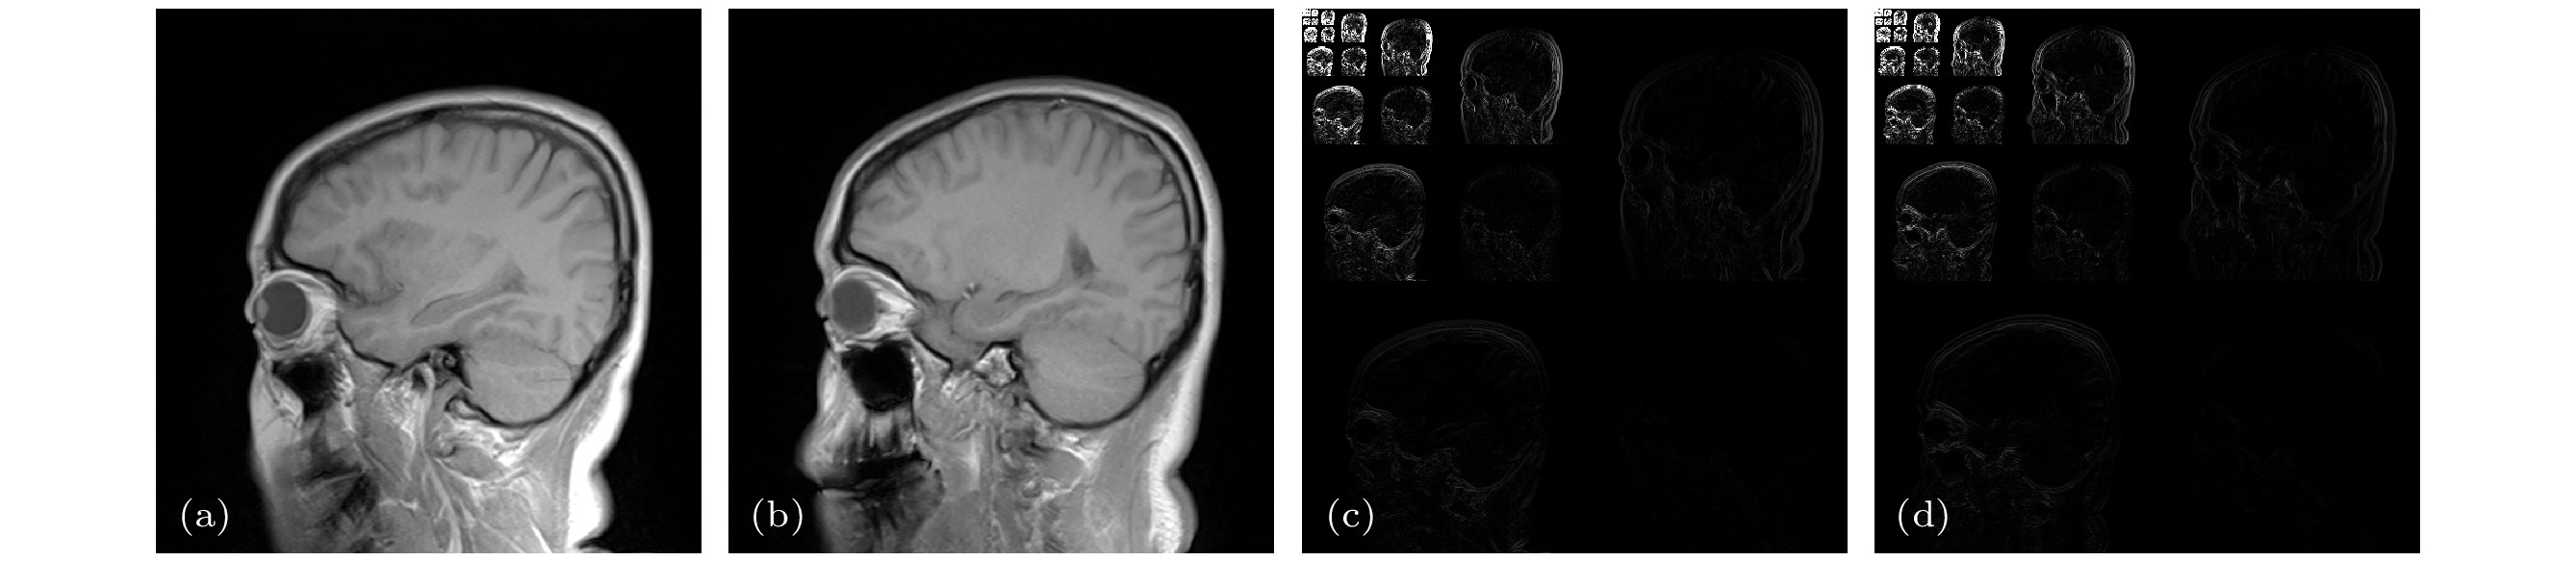

基于深度学习的磁共振成像(magnetic resonance imaging, MRI)方法需要大规模、高质量的病患数据样本集进行预训练. 然而, 由于病患隐私及设备等因素限制, 获取大规模、高质量的磁共振数据集在实际临床应用中面临挑战. 本文提出一种新的基于深度学习的欠采样磁共振图像重建方法, 该方法无需预训练、不依赖训练数据集, 而是充分利用待重建的目标MR图像的结构先验和支撑先验, 并将其引入深度图像先验(deep image prior, DIP)框架, 从而削减对训练数据集的依赖, 提升学习效率. 基于参考图像与目标图像的相似性, 采用高分辨率参考图像作为深度网络输入, 将结构先验信息引入网络; 将参考图像在小波域中幅值大的系数索引集作为目标图像的已知支撑集, 构造正则化约束项, 将网络训练转化为网络参数的最优化求解过程. 实验结果表明, 本文方法可由欠采样 k空间数据重建得到更精确的磁共振图像, 且在保留组织特征、细节纹理方面具有明显优势.Magnetic resonance imaging (MRI) method based on deep learning needs large-quantity and high-quality patient-based datasets for pre-training. However, this is a challenge to the clinical applications because it is difficult to obtain a sufficient quantity of patient-based MR datasets due to the limitation of equipment and patient privacy concerns. In this paper, we propose a novel undersampled MRI reconstruction method based on deep learning. This method does not require any pre-training procedures and does not depend on training datasets. The proposed method is inspired by the traditional deep image prior (DIP) framework, and integrates the structure prior and support prior of the target MR image to improve the efficiency of learning. Based on the similarity between the reference image and the target image, the high-resolution reference image obtained in advance is used as the network input, thereby incorporating the structural prior information into network. By taking the coefficient index set of the reference image with large amplitude in the wavelet domain as the known support of the target image, the regularization constraint term is constructed, and the network training is transformed into the optimization process of network parameters. Experimental results show that the proposed method can obtain more accurate reconstructions from undersampled k-space data, and has obvious advantages in preserving tissue features and detailed texture.